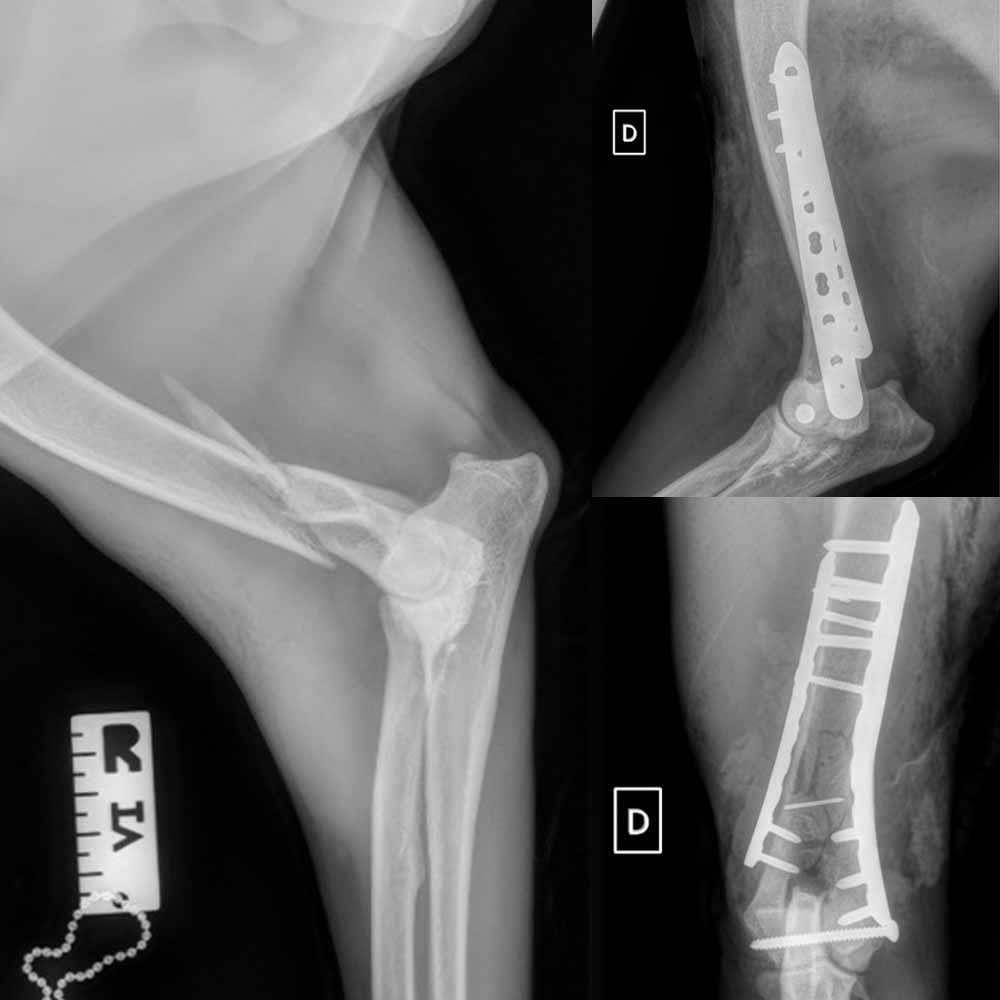

fibrosarcome ctx500